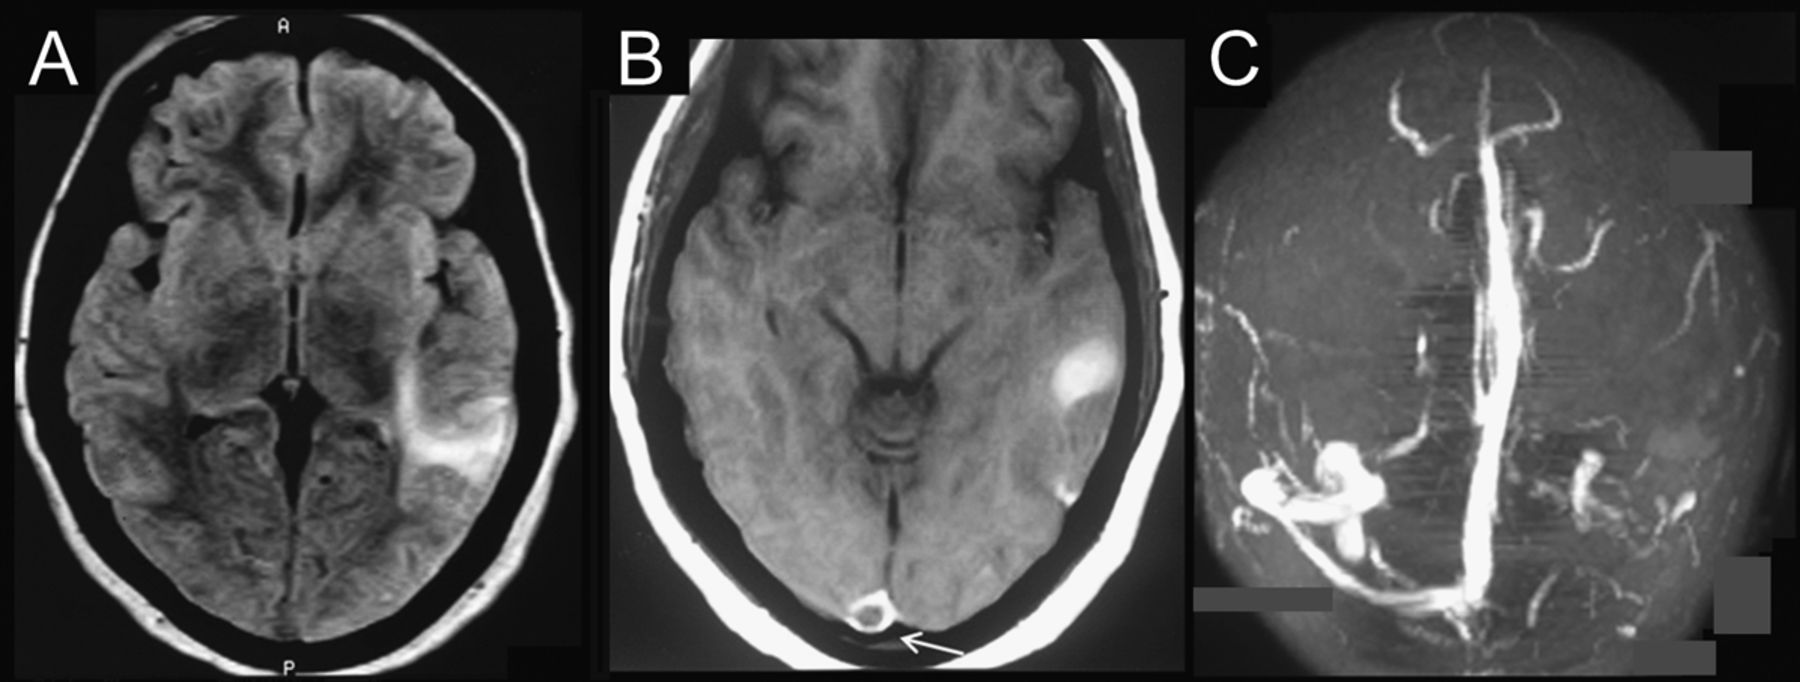

图2 Gadolinium-enhanced MRI大脑和磁共振造影术

MRI脑(41 T1序列显示)(一)急性左颞出血性梗塞和(B)充盈缺损上矢状窦(箭头)gadolinium-enhanced T1序列。(C)磁共振造影术显示左乙状结肠和横窦血栓形成。

一个18岁的女人出现头痛、局部癫痫发作,左眼的视力下降20天。眼底检查发现两国视神经乳头水肿与大型premacular sub-internal限制膜和左眼subhyaloid出血(图1一个)。核磁共振大脑显示出血性梗塞的左颞叶(图2中,A和B)。磁共振造影术显示左横和乙状窦血栓形成(图2 c)。Terson综合征的诊断1(玻璃体出血)。促凝血的检查是阴性病人改善与保守的管理2(图1 b)。尽管Terson与蛛网膜下腔出血综合症报道,与皮质静脉窦血栓形成的发生是罕见的。